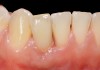

Problem: The implant is placed too facially, and there is significant labial gingival recession, contour change, and mucosal discoloration around the implant, abutment, and crown (Figure 3 and Figure 4). The implant attachment apparatus is intact and healthy, but the patient has a thin periodontal phenotype.

The following case report provides an example of this case scenario: A 28-year-old white female patient presented with her maxillary right lateral incisor significantly longer than the contralateral tooth following restoration of an existing crown that was 10 years old (Figure 3). The patient was dissatisfied with the esthetic appearance of the restoration due to the increased length, recession of the gingival tissues, and discoloration of the surrounding mucosa (Figure 4). Similar to case scenario No. 1, the first step in treatment was to decoronate the healthy implant by placing a flat surgical cover screw and employing a provisional resin-bonded-retained (RBR) prosthesis as a transitional fixed restoration (Figure 5 and Figure 6). The gingival augmentation in situ was allowed to take place for 2 to 3 weeks and was evaluated after that time (Figure 7).

Fig 3. A patient presented with a high smile line and midfacial recession of the maxillary right lateral incisor as evidenced by the increased tooth length compared with the contralateral lateral incisor.

Fig 4. Intraoral view of tooth No. 7 with the gingival zenith more apical than the adjacent central incisor and canine tooth.